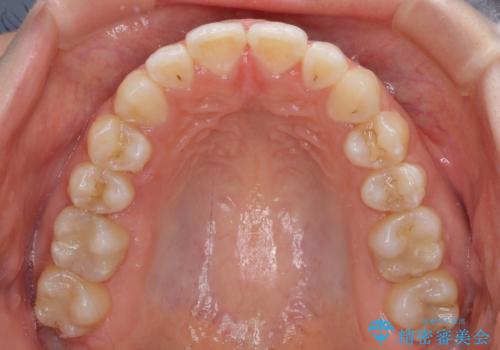

【モニター】オープンバイトをインビザラインで矯正治療

- 前歯の上下スペースによる食べにくさを気にして来院された患者様です。

インビザラインにより上下の前歯の隙間を閉じていくこととしました。

前歯のデコボコの解消と並行して上下の奥歯を圧下させるようにすることで、前歯を接触させるように計画しました。

上下の隙間に舌が入り込むことがオープンバイトの原因であったため、舌の筋肉のトレーニングも並行して行い、後戻りの抑制を図りました。